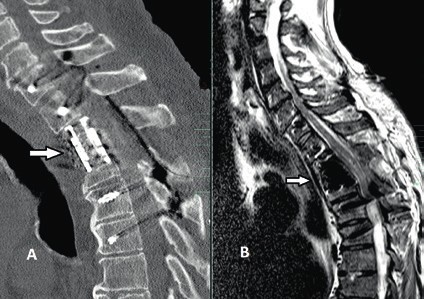

Prinzipiell richtet sich die Entscheidung, welche operative Versorgung durchgeführt wird, nach Ausmaß und Art der Verletzung. Für die Stabilisierung der dorsalen Säule reicht im Falle einer stabilen ventralen Säule die dorsale Instrumentierung aus. Hier gewährleisten dorsale Pedikelschrauben, die mit einem Stab verbunden sind, eine gute Wiederherstellung der Stabilität (Abb. 2). Im Falle einer instabilen ventralen Säule ist hingegen eine Implantation von Wirbelkörperersatz und eine dorsoventrale Segmentversteifung indiziert (Abb. 3). Die entwickelten minimalinvasiven Techniken – zum Beispiel die transkutane Pedikelschraubenimplantation oder der Wirbelkörperersatz durch endoskopische Thorakotomie – haben dazu geführt, dass das Wundgebiet und die operationsbedingte Gewebeschädigung reduziert werden und somit eine Belastungsreduktion für den Körper erzielt wird. Dieser Aspekt ist insbesondere bei älteren Patienten mit multiplen Begleiterkrankungen von Vorteil. Im Falle einer osteoporotischen Wirbelsäule werden die implantierten Pedikelschrauben zementiert (Abb. 4). Auch hier erlaubt die Entwicklung fenestrierter Schrauben eine optimale Möglichkeit der Zementapplikation.